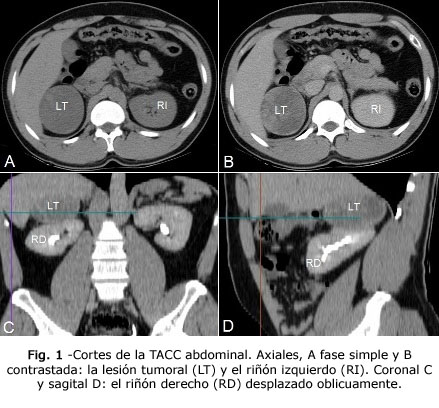

La tomografía axial computarizada contrastada (TACC) tóraco - abdominal, no reveló alteraciones cardiacas ni pleuro- pulmonares. Verificó la lesión tumoral, de 6 x 7 cm, bien delimitada y con densidades variables, en proyección de la glándula suprarrenal derecha, que desplazaba el riñón hacia abajo y con orientación oblicua. El tumor realzó ligeramente y de forma heterogénea. El riñón izquierdo era normal (Fig. 1).

La TACC y la resonancia magnética nuclear, carecen de especificidad para distinguir el OS de otros tumores suprarrenales, aunque ciertos detalles de la TACC incrementan el índice de sospecha.(5) Por ejemplo los OS realzan muy poco, menos de 10 unidades Hounsfield (UH) debido a su alto contenido lipídico. Los carcinomas suprarrenales y las lesiones metastásicas, muestran elevadas cifras de realce (> 21 UH) y la mayoría de los feocromocitomas (> 110 UH).(6) Otros autores plantean que en la mayoría de los OS, el realce es heterogéneo.(1,4) La lesión tumoral del paciente de esta presentación, mostró realce heterogéneo e inferior a 20 UH, por lo cual coincide con los autores consultados.